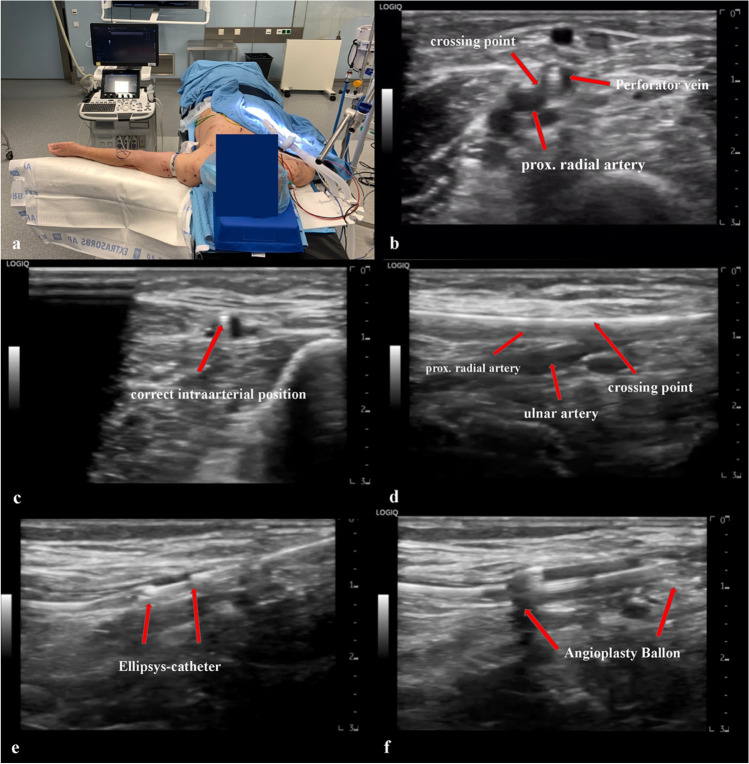

Fig. 4.

Overview of the procedure: a preoperative positioning and positioning of the ultrasound device; b ultrasound cross-section, proximal forearm, showing the crossing point between the perforating vein and the proximal radial artery; c ultrasound cross-section forearm, checking the guidewire for correct intra-arterial position. The arrow marks the guidewire (anechoic point); d ultrasound longitudinal section prox. forearm, visualization of the brachialis bifurcation with correct intra-arterial position of the guidewire; e ultrasound longitudinal section prox. forearm, positioning of the Ellipsys catheter; f ultrasound longitudinal section prox. forearm, PTA of the anastomosis using a 5 × 20 mm monorail balloon after successful application of the Ellipsys catheter

After successfully puncturing the artery and the verification of the correct position of the guide wire (Fig. 4c, d), the procedure can usually be completed easily. Intraoperatively, no X-rays or contrast agents are necessary.

The procedure is performed in supine position and under plexus anesthesia. The arm, which is designated for the AFV creation, is placed on a side table with the palm facing upward. Before sterile washing, a tourniquet is attached to the proximal upper arm. The ultrasound device is placed opposite the surgeon (Fig. 4a). The preoperative setting is shown in Figs. 5 and 6.

After the disinfection and sterilization of the arm, the anatomical conditions are examined again by ultrasound. The puncture should be done by a micropuncture needle. We recommend an access of about 1 to 2 cm max. above the division of the perforator vein. This allows the procedure to be successful despite the perforator vein being at an unfavorable angle in comparison to the superficial veins. Subsequently, the tip of the needle must be positioned centrally in the vessel with the aid of an ultrasound (hyperechoic point in the vessel (Fig. 4b) after which the needle is gradually advanced under sonographic control. The tip of the needle is navigated from the superficial arm vein into the perforator vein. After the needle has been positioned in the perforator vein, the crossing point to the proximal radial artery must be found, which may not exceed 1.5 mm (Fig. 4b). Depending on the position of the perforator vein, the proximal radial artery can then be punctured. After the successful verification of the correct intraarterial needle tip position (sonographic control in transverse and longitudinal sections) (Fig. 4c, d), a 0.018-in guidewire is inserted into the radial artery. Subsequently, 3000 international units of heparin is intravenously administered to the patients. The next step is to remove the micropuncture needle and a 6 Fr. a slender sheath (reduced outer diameter) is inserted into the radial artery via the 0.018-inch guidewire.

The introducer is left inside and the wire located over the introducer is exchanged for a 0.014-in wire. Once the exchange is made, the introducer is removed. The next step is for the Ellipsys® catheter to be inserted, connected to the generator, and to be positioned under sonographic control. It is important that the catheter tip is placed into the radial artery and that the catheter base can be inserted in the perforator vein (Fig. 4e). Once the correct position is successfully verified, the Ellipsys® catheter can be closed and the distance between the artery and vein can now be read off the generator. A distance of 0 mm would be an indication that the arterial and venous vascular wall is not located between the Ellipsys® catheter. Standard values are between 0.1 and 0.9 mm. After verifying the distance, the catheter is activated and a tissue-fused permanent anastomosis is created. The Ellipsys® catheter can then be removed. After execution of the Ellipsys catheter, a palpable thrill can be noticed.

To increase the primary patency, a simultaneous angioplasty of the anastomosis is recommended. The arteriovenous anastomosis is dilated for at least 90 s (Fig. 4f) with a 5 × 20 mm monorail balloon. The deep venous system usually remains untouched. Thereafter, the materials are removed and the puncture is gently pressed off for 3–5 min. In addition, the puncture site is secured with steri-strips and covered by a sterile plaster.